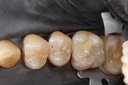

Larry Fujioka #11-12 pre-op

Larry Fujioka #12 pre-op